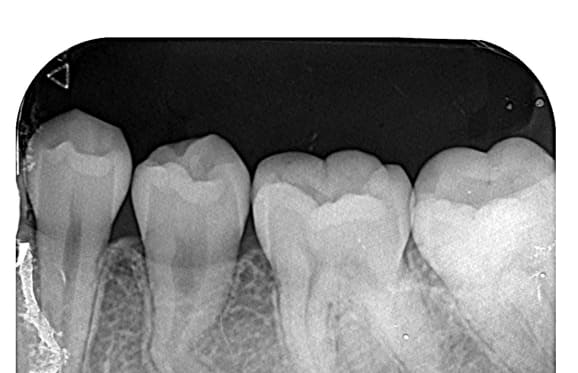

● 下の顎の親知らず抜歯 1回法

藤沢デンタルオフィスの親知らず抜歯

● 下の顎の親知らず抜歯 2回法

01 神経に近い位置に親知らずの根が存在

02 親知らずの頭の部分だけ抜歯

03 親知らずの根の部分が神経から離れる

下の顎の親知らずの抜歯では、神経の損傷リスクを考えて2回に分けて抜歯する場合があります。 また、麻酔が効きにくい場合にも、同様に2回に分けて抜歯します。